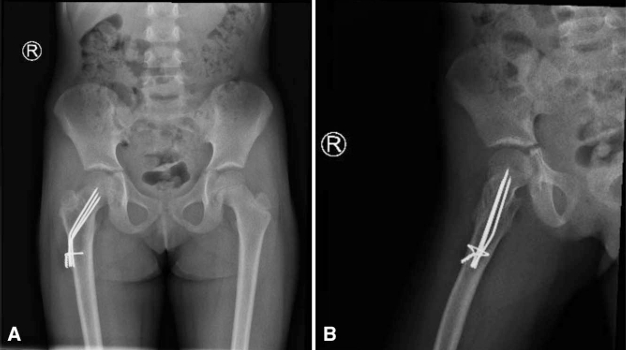

一名 5 岁女童因右下肢外伤后 3 周出现右髋疼痛并伴有跛行而就诊于我院急诊科。体格检查发现,其右髋存在疼痛,且在髋关节旋转时疼痛加重。影像学检查显示,右侧股骨颈可见一大型溶骨性病变,向转子区延伸,并伴有股骨颈应力性骨折及内翻移位(图 1 和图 2)。